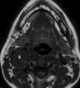

Multiple nerve tumors